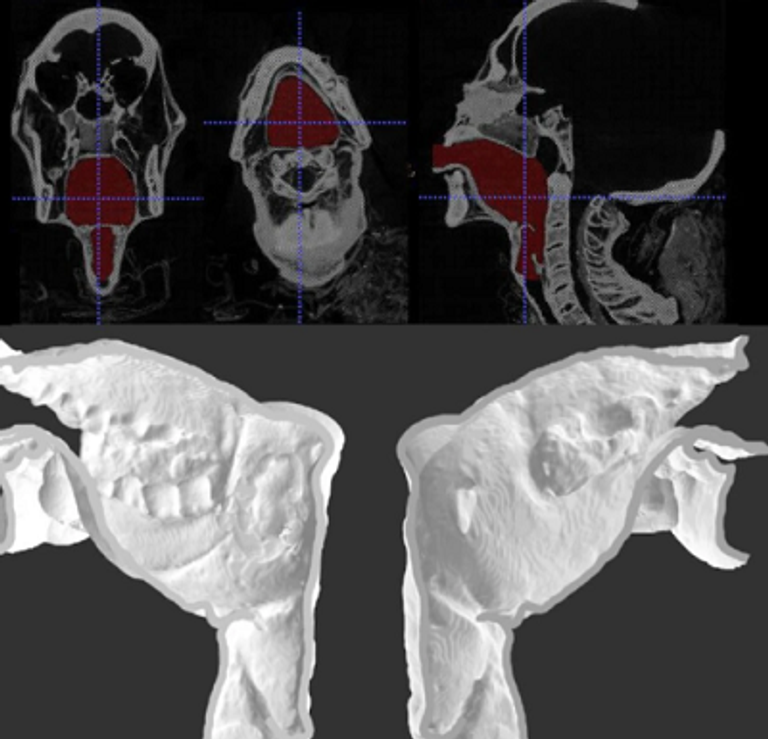

وكانت دورية "ساينتيفك ريبورتس" نشرت في 23 يناير/كانون الثاني الماضي، دراسة علمية تعلن تمكن باحثين بريطانيين من إعادة إنتاج صوت الكاهن الفرعوني "نيسيامون"، المتوفى منذ 3000 عام، والذي توجد مومياه في متحف مدينة ليدز الإنجليزية، وذلك باستخدام نسخة ثلاثية الأبعاد من الحنجرة.

وأشار التقرير إلى أن الجزء المسؤول عن إصدار الصوت وجد في حالة حفظ استثنائية، وهي حالة نادرة لمثل تلك الأجزاء التشريحية بالجسم، وساعد ذلك الباحثين على تحديد كل المقاييس والأبعاد التشريحية لهذا الجزء، ثم استخدموا تقنية الطباعة ثلاثية الأبعاد لإنتاج نموذج أطلقوا عليه "حنجرة إلكترونية".

وبالتعاون مع بعض العلماء من تخصصات أخرى مثل الهندسة والصوتيات تمكنوا من وضع تصورات لطبقة الصوت التي يمكن أن تخرج من هذا التركيب التشريحي.